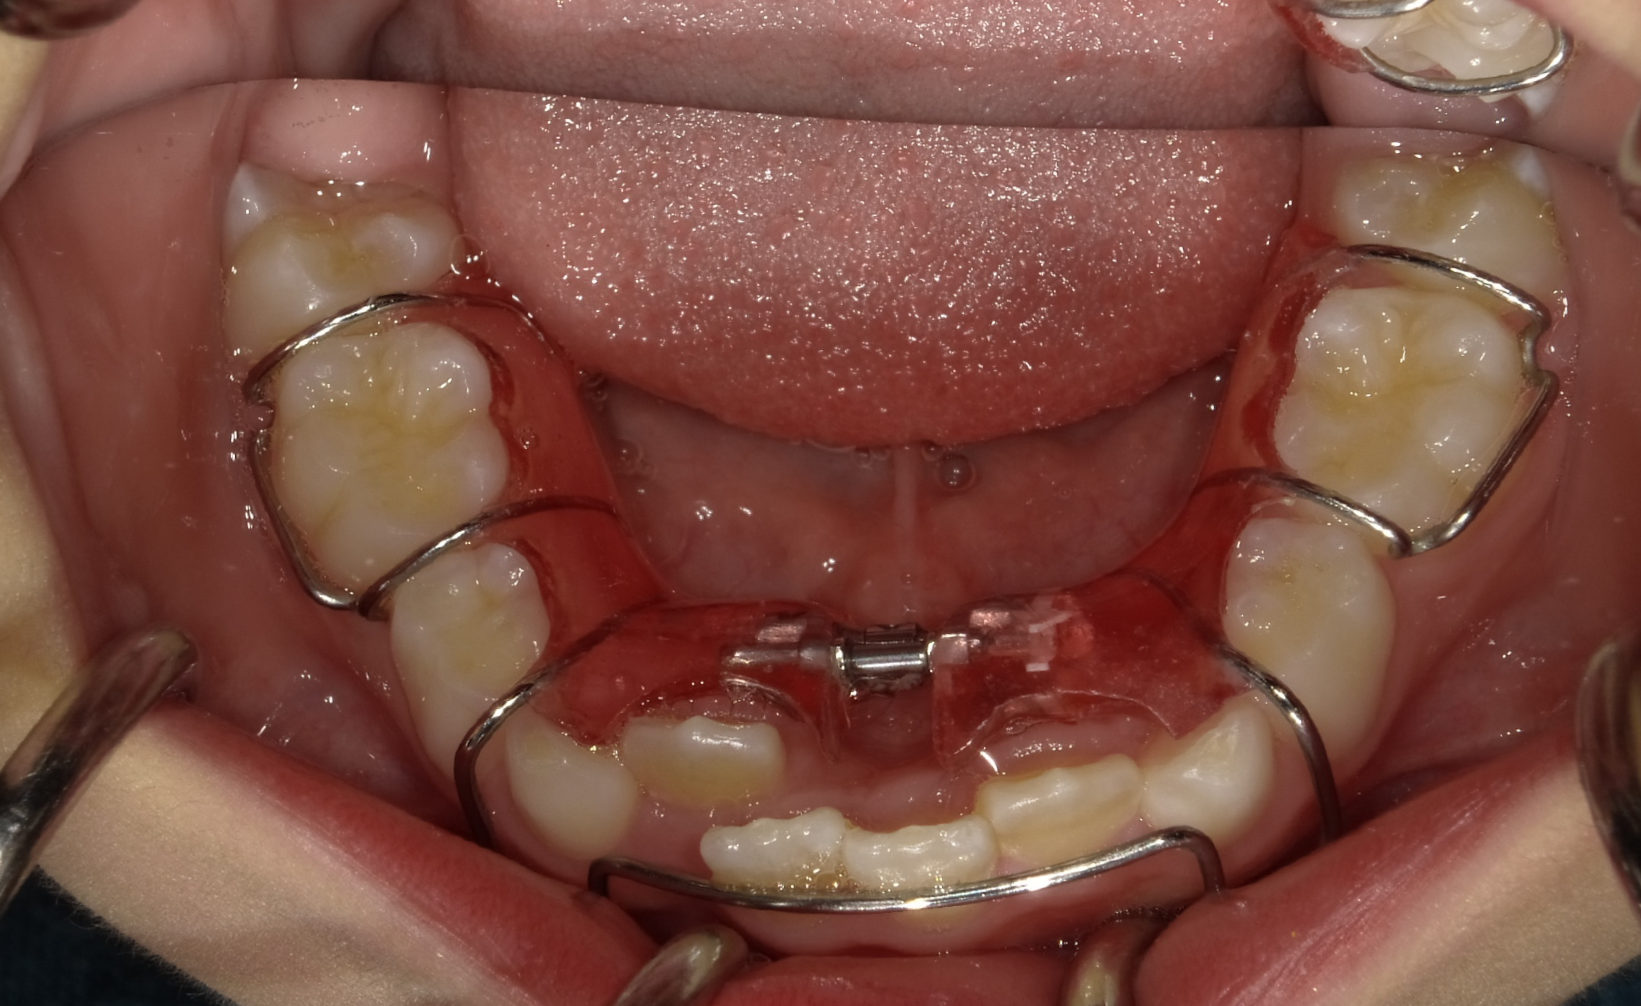

1期矯正

まずは拡大床という装置を使い、凸凹の改善を目指します。

1期矯正の経過

時間はかかりますが、だいぶ凸凹が改善してきました。しかしまだ正面か見ると下の歯が見えません。

今回は上の歯が出過ぎているというより、下の顎は引っ込みすぎていると診断し、下顎を前に誘導する装置を使用します。